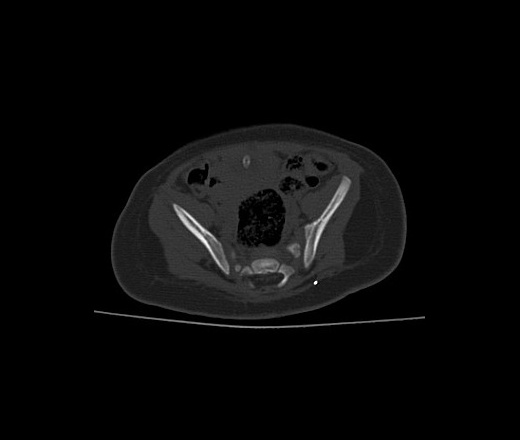

Ребенку 3 недели, оперирована по поводу спинномозговой грыжи, менингоцеле. Послеоперационный период с осложнениями - нагноение, рана "разваливается". На контрольной КТ в подкожножировом слое - достаточно далеко от зоны операции, и на поверхности раны - множественные мелкие (0,5-1,5 мм) округлые включения металлической плотности (до 3071 - предел аппарата). Нейрохирурги обрабатывали рану ксероформом, может ли он так выглядеть?

Впечатление сетки. При вентральных грыжах используют трансплантаты, может и тут такое же?

Пластинку укладывали, но она намного меньше по размерам. В реконструкциях на сетку не похоже - беспорядочно разбросанные "кругляши" разного размера.

на 2-м скане у ребенка "инородное тело" на поверхности кожи, просто глянь что-это и все))

Это не совсем кожа - гнойная рана, с гноем и сукровицей, кожа отваливается кусками, на настоящий момент уже вся отвалилась. Что-нибудь там рассмотреть несколько проблематично, во всяком случае хирурги при перевязке ничего не заметили.